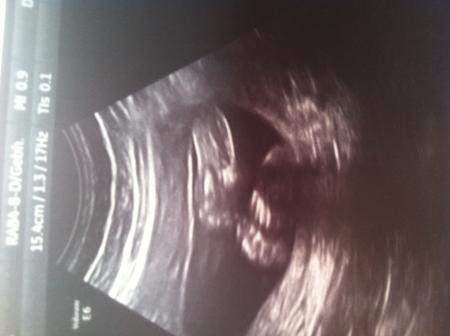

Ich bin gerade so Mega glücklich und erleichtert:) Es gab absolut keine Auffälligkeiten.. Der kleine Prinz ist ganz prächtig entwickelt:) bin heute 23+0 also 24. Woche:) der kleine ist 28cm groß und wiegt 600g man hat der sich entwickelt:-) Ich bin richtig stolz auf den kleinen Wurm.. Hier noch ein Bild wer genau hin sieht,erkennt alles:) Sieht aus als wenn er nuckelt :-))

Das freut mich das alles in ordnung ist. Hab auf dem bildchen dein prinzen erkennen können und den finger im mund :o) Wow echt wahnsinn wie gross er schon ist